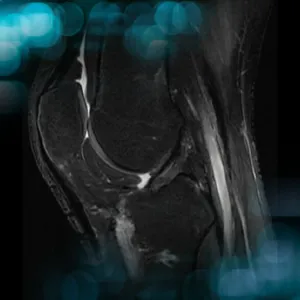

The goals of this clinical case are to discuss the different therapeutic options in cases of ACL graft failure, and to propose an innovative technique.

The goals of this clinical case are to discuss the physical examination of a multiligament knee injury and its surgical treatment.